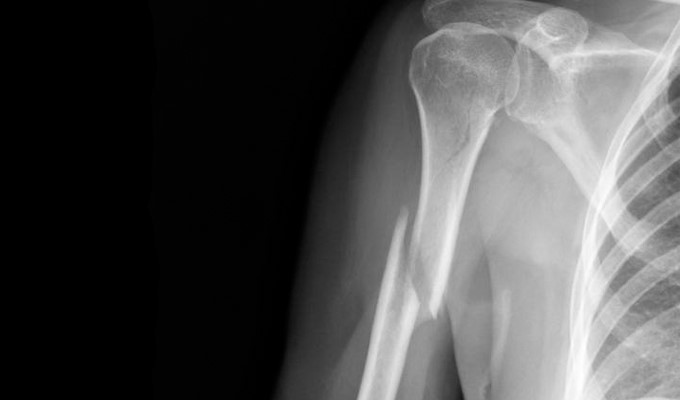

Следующим шагом является рентгеноскопия травмированной конечности. При недостаточности этого метода, применяется магниторезонансная томография либо ультразвуковое обследование. Для полной картины понимания происшедшей травматизации и точности диагностирования пострадавшим сдаются анализы.